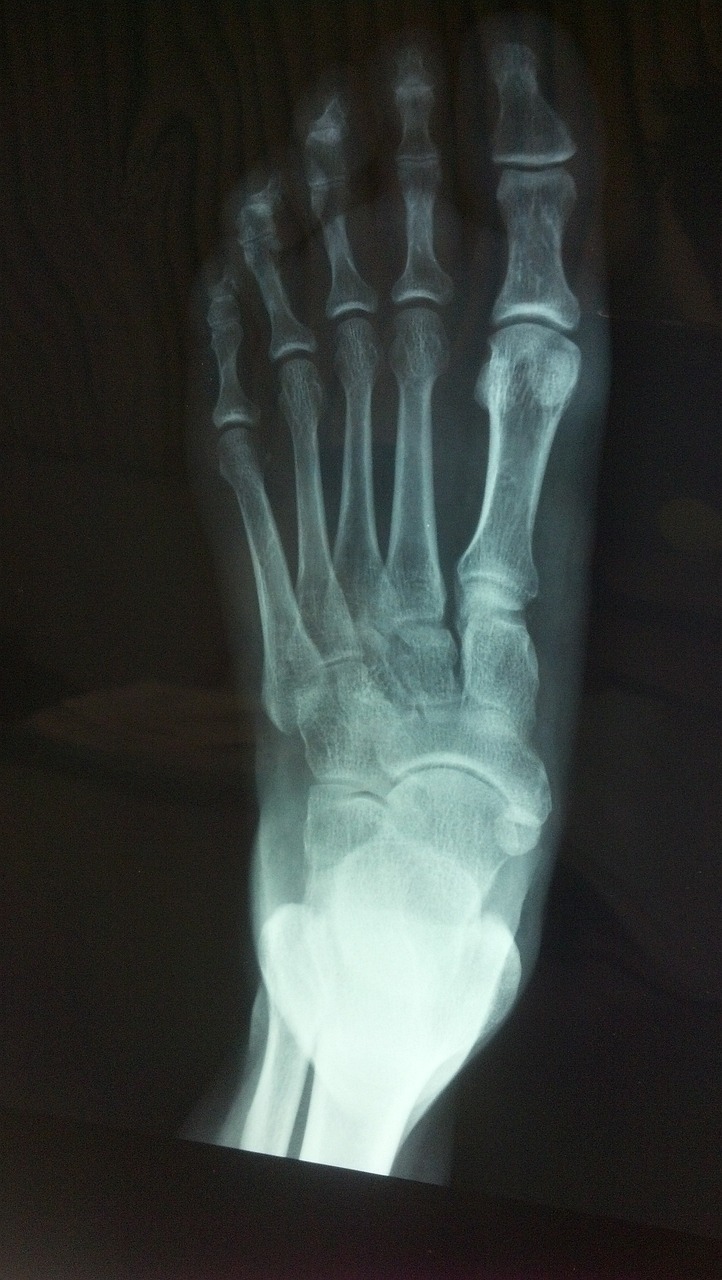

무지외반증 판단 기준

무지외반증의 판단 기준은 2가지입니다.

첫번째는 발가락뼈의 각도인데요.

발가락뼈가 15도 정도 기운 것까지는 정상 각도입니다.

그 이상으로 벌어지면 무지외반증입니다.

두번째는 발등뼈끼리의 간격의 각도입니다.

2번째 발등뼈와 1번째 발등뼈의 간격이 9도 이상 벌어지면 무지외반증입니다.